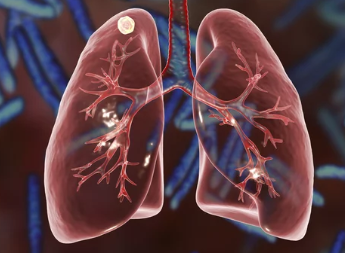

기침, 가래, 미열, 체중 감소... 혹시 결핵은 아닐까 걱정되시나요? 결핵은 결핵균에 의해 발생하는 감염병으로, 주로 폐를 침범하지만 다른 장기로도 퍼질 수 있습니다. 결핵은 과거에는 '불치병'으로 여겨졌지만, 현대 의학의 발전으로 조기에 발견하고 치료하면 완치가 가능합니다. 하지만 초기 증상이 감기와 비슷하여 방치하기 쉽고, 전염성이 있어 주변 사람들에게도 영향을 미칠 수 있으므로 주의가 필요합니다.

결핵은 결핵균에 감염된 사람이 기침, 재채기, 대화 등을 할 때 공기 중으로 배출된 결핵균이 다른 사람의 호흡기를 통해 전파됩니다. 결핵균은 면역력이 약한 사람에게 쉽게 감염되며, 특히 좁고 밀폐된 공간에서 장시간 함께 생활하는 경우 감염 위험이 높아집니다.